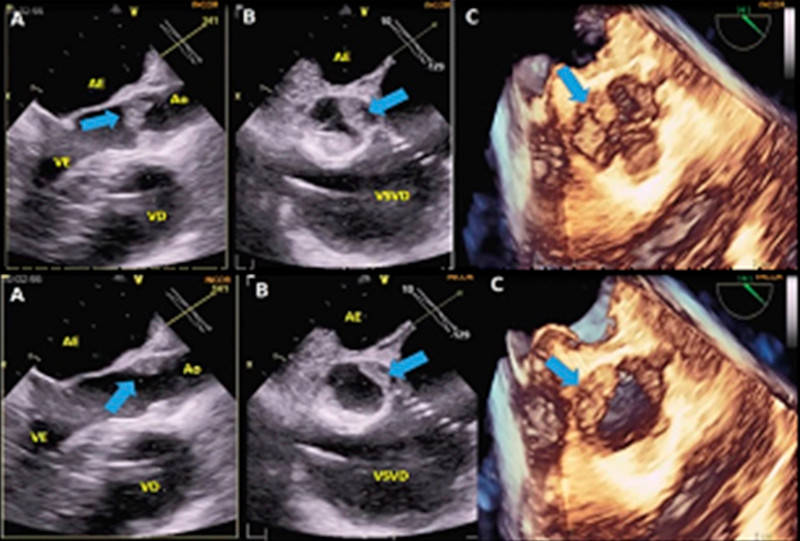

Ya en el periodo intraoperatorio, el ETE 3D demostró VAo con engrosamiento importante, con múltiples imágenes homogéneas, hipoecogénicas, móviles y de contornos irregulares en la proyección ventricular y aórtica, de 15 × 6 mm, con aspecto sugestivo de vegetaciones adheridas a los velos, que ocasionaban reducción de la superficie de coaptación de los mismos (Figuras 1, 2, 3). Además de observó una velocidad máxima del jet transvalvular de 3,3 m/s; gradiente transvalvular medio de 21 mmHg, área valvular por la ecuación de continuidad y planimetría de 1,3 cm², con insuficiencia valvular de grado mínimo. Sin embargo, debido a la evidencia de las alteraciones morfológicas de la VAo, en vigencia del riesgo de fenómenos embólicos, se realizó un reemplazo de la VAo con una prótesis mecánica N° 23. Ambos procedimientos fueron realizados sin complicaciones. Al análisis macroscópico de la VAo se evidenció una opacificación de las válvulas semilunares con gran cantidad de material amorfo rojo oscuro adherido, de aspecto irregular (Figura 4). El examen anatomopatológico mostró un extenso trombo de fibrina con áreas de leucocitos y hematíes, compatible con endocarditis trombótica no infecciosa; las semilunares exhibían discreto engrosamiento fibroconjuntivo (Figuras 5 y 6). A los 21 días de los procedimientos, debido a la buena evolución, con mejora de la disnea sin necesidad de oxígeno suplementario, se optó por mantener la anticoagulación oral y dar el alta hospitalaria. En el seguimiento de 6 meses, el paciente mantenía estabilidad clínica, con disnea a los esfuerzos no habituales, y sin nuevos eventos embólicos.

En el caso descrito no hubo sospecha de lesión de la VAo por el ETT 2D, que fue únicamente diagnosticada por el ETE 3D intraoperatorio. Por ello, además de la tromboendarterectomia de la AP, fue realizado el reemplazo de la VAo, debido a la presencia de las vegetaciones (endocarditis no infecciosa), historia previa de SAF y de eventos tromboembólicos. La ecocardiografía 3D fue en este caso una herramienta fundamental.